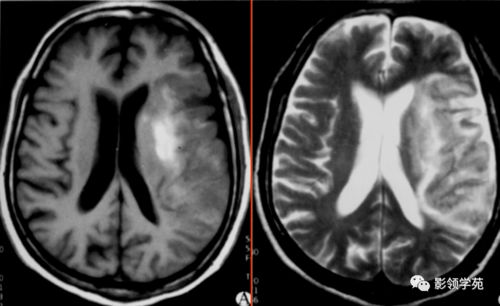

针对以上因素,我们提出以下建议供高危人群参考。利用风险评估工具如Framingham评分,结合年龄、血压、血脂等指标进行早期风险识别。通过实验室检测,重点监测血脂四项、血糖及高敏C反应蛋白等关键指标。通过影像学检查,如颈动脉超声、心脏彩超等,可以直观评估血管状态。